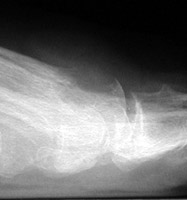

Gout: AP- Erosions 1st MTP joint with tophiGout: AP- Erosions 1st MTP joint with tophiTophaceus Gout: LateralTophaceus Gout: APGOUT is caused by monosodium urate or uric acid crystal deposition within cartilage, bone, or periarticular tissues.

Acute, episodic soft tissue swelling may represent the earliest radiographic sign. Later, sharp, round or oval marginal joint erosions with sclerotic borders are classically seen with gout. These findings most commonly occur along the dorsum of the foot. Associated soft tissue tophi or intraosseous nodules may be present. "Overhanging margin" occur where the bone resorbs beneath a tophaceous nodule. Joint spaces are usually preserved, but ankylosis may rarely occur with advanced stages of gout. The aforementioned findings may be in different stages of progression with any given patient.